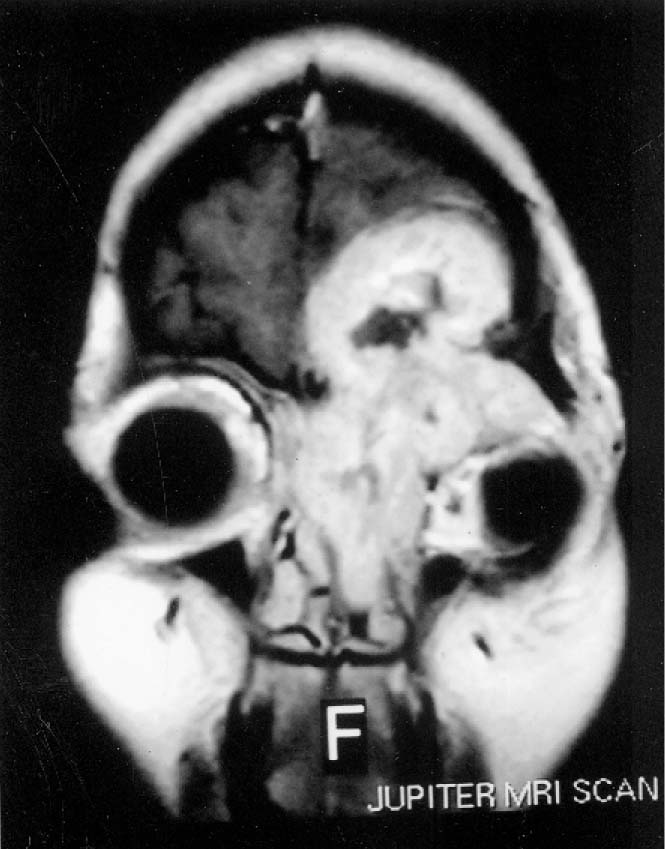

Glomus Jugulare Paraganglioma The Neurosurgical Atlas, by Aaron Cohen Salt And Pepper Appearance Paraganglioma the salt and pepper sign is used to describe a typical mri appearance of some highly vascular tumors that contain foci of. ct and mri findings of the vagal paraganglioma are similar to those of the carotid body tumor: paragangliomas of the head and neck originate most commonly from the paraganglia within the carotid body, vagal nerve,. Salt And Pepper Appearance Paraganglioma.

Saltandpepper appearance of glomus tumour. Axial T1 sequence shows Salt And Pepper Appearance Paraganglioma the salt and pepper sign is used to describe a typical mri appearance of some highly vascular tumours that contain foci of. the salt and pepper sign is used to describe a typical mri appearance of some highly vascular tumors that contain foci of. paragangliomas show low to intermediate intensity in t1 signal and high. paragangliomas. Salt And Pepper Appearance Paraganglioma.